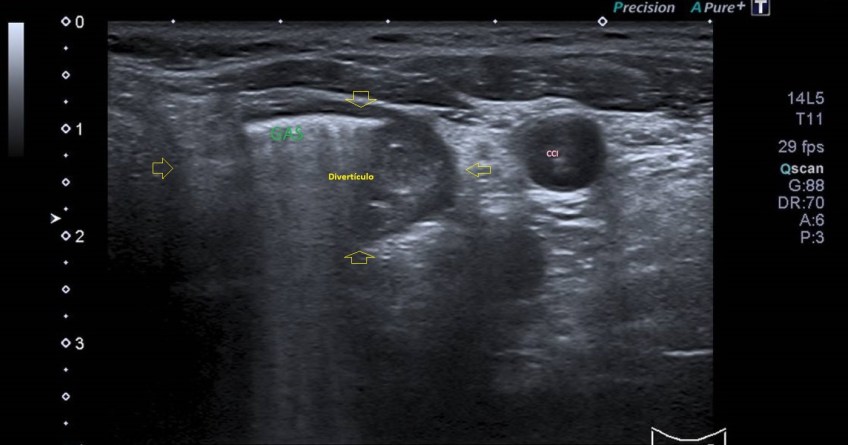

Comenzamos el estudio para visualizar la glándula tiroides de una forma global, como puedes ver en la imagen 1.

En la imagen 2, al lado de la zona donde visualizamos normalmente el esófago se observa una imagen más grande, no tan circular y con gas en su interior. Es de un tamaño considerable, heterogénea por el gas interno. Es una imagen anormal que requiere evaluación del radiólogo.

En la imagen 2 puedes ver el esófago, que nos vale de guía anatómica y aquí es muy importante el asterisco verde que marca el gas dentro del divertículo, en esa localización la presencia de gas es completamente anómala.

Realizamos protocolo para el estudio de cuello por ecografía y observamos que esa imagen tiene continuidad con el esófago. Tiene gas en su interior por lo que el radiólogo lo informó como probable divertículo esofágico. Este divertículo es conocido como divertículo esofágico de Killiam-Jamieson.

La sonda está en transversal al lóbulo tiroideo izquierdo. Se visualiza el esófago (E) y divertículo de Killiam-Jamieson.